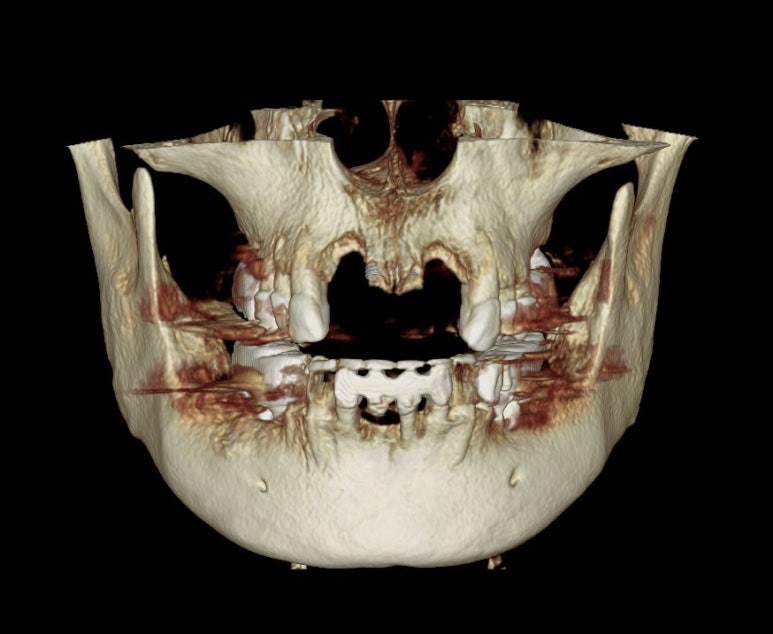

약 6주 뒤에 CT 촬영을 하였습니다.

위턱 앞니 부위에 남은 잇몸뼈가 거의 없었습니다.

가장 이해하기 쉬운 CT 자료입니다.

얼굴뼈의 아래 절반정도만 찍히는 치과용 CBCT를 사용하여 촬영 후 영상을 3D로 재건한 사진입니다.

보시다시피 앞니 네개가 제거는 되었지만, 정작 뼈는 가운데 부분만 말안장처럼 남아있어요.

가운데 남은 요 부위에 두개의 임플란트를 심어보기로 계획했어요.

그리고 양 옆에 비어있는 부분은 뼈이식을 무지하게 많이 해보기로 했습니다.